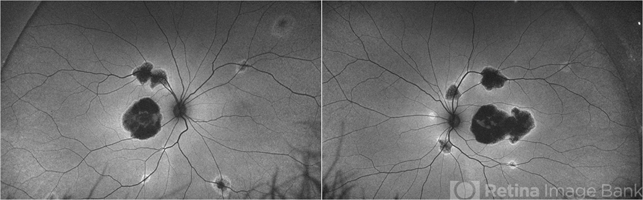

- fundus autofluorescence (FAF), central areolar choroidal dystrophy (CACD), hereditary retinal degeneration

- Fundus autofluorescence pictures of a 37-year-old male with CACD. The patient has visual acuity of 1/18 in the right eye and 6/30 in the left eye. Full-field ERG was normal under photopic and scotopic conditions.